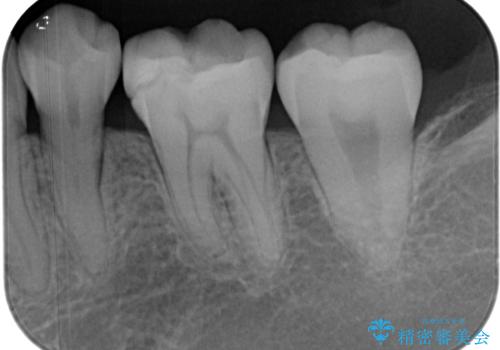

- 他院で保険の詰め物を行い、割れたためやり替えたいとのことで来院された患者様です。

セラミックの詰め物(セラミックインレー)とセラミックにプラスチックを混ぜた詰め物(ハイブリッドインレー)の二種類のメリット、デメリットを説明したうえで、患者様のご希望でハイブリッドインレーで治療をしていくことになりました。

拡大鏡視野下で、保険の詰め物、虫歯の除去を行い、ハイブリッドインレーに適した形に整えました。